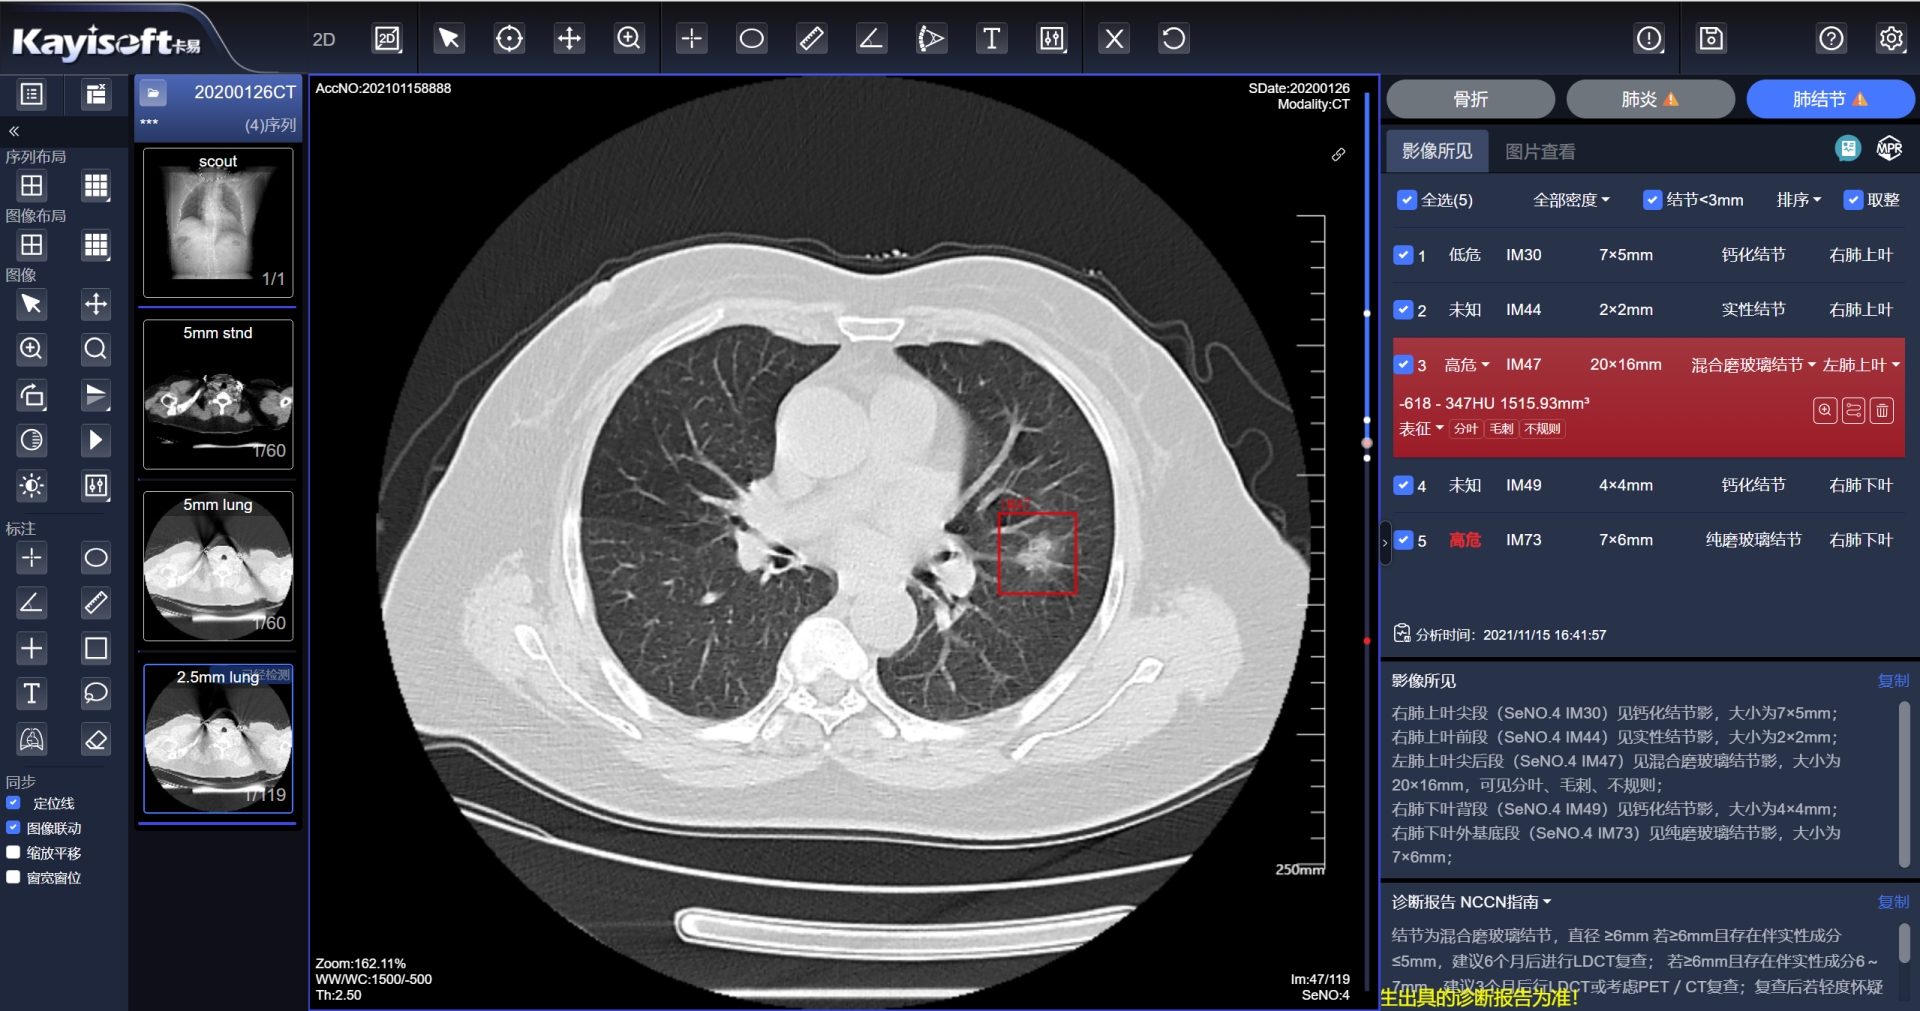

¡®¿µ½¡ÔƼ졯ƽ̨µÄÁÁµãÔÚÓÚÆäǿʢµÄAIÖÇÄÜÕï¶Ï¹¦Ð§¡£¡£ ¡£¡£¡£¡£¡£¸Ãƽ̨Äܹ»×Ô¶¯Ê¶±ðÓ°Ïñ£¬£¬ £¬ £¬ £¬Ìṩ²¡ÔîÖÇÄÜÕï¶ÏÆÊÎö£¬£¬ £¬ £¬ £¬²¢ÌìÉúͼÎĽṹ»¯±¨¸æ¡£¡£ ¡£¡£¡£¡£¡£Ïà½ÏÓڹŰåµÄÈ˹¤Á÷³Ì£¬£¬ £¬ £¬ £¬Õâһϵͳ²»µ«ÄܽÚÔ¼´ó×Úʱ¼ä£¬£¬ £¬ £¬ £¬Ìá¸ßЧÂÊ£¬£¬ £¬ £¬ £¬»¹ÄÜÔÚÒ»¶¨Ë®Æ½ÉϱÜÃ⩼ìºÍÎóÕïµÄ±¬·¢¡£¡£ ¡£¡£¡£¡£¡£ÓÉ´Ë£¬£¬ £¬ £¬ £¬Ò½ÁÆ×ÊÔ´Äܹ»ÊµÏÖ¼¯Öй²ÏíºÍ¸ßЧÉèÖ㬣¬ £¬ £¬ £¬Èû¼ÕßµÃÒÔÏíÊܼÒÃſڵġ°AI+¡±¿µ½¡ÊØ»¤¡£¡£ ¡£¡£¡£¡£¡£

»ùÓÚÇøÓòÓ°ÏñÔÆµÄCT·Î½á½ÚAIÆÊÎö

ÕâÒ»Ó¦ÓÃͨ¹ýÓ°ÏñÊý¾ÝÔÆ»¯ÖÎÀíÊý¾ÝͳһÊÕÂÞ£¬£¬ £¬ £¬ £¬ÊµÏÖÒÔÊý¾ÝΪ»ù´¡£¬£¬ £¬ £¬ £¬ÍŽá AI ÆÊÎöЧÀÍ£¬£¬ £¬ £¬ £¬ÊµÏַνá½ÚÖÇÄܱê×¢£¬£¬ £¬ £¬ £¬½µµÍ©Õï¡¢ÎóÕïµÄ¸ÅÂÊ£¬£¬ £¬ £¬ £¬½«ÕïÆ¬Ê±¼ä´Ó¹Å°åµÄ5·ÖÖÓ£¬£¬ £¬ £¬ £¬Ëõ¶Ìµ½ÁË2-3·ÖÖÓ¡£¡£ ¡£¡£¡£¡£¡£

640.png